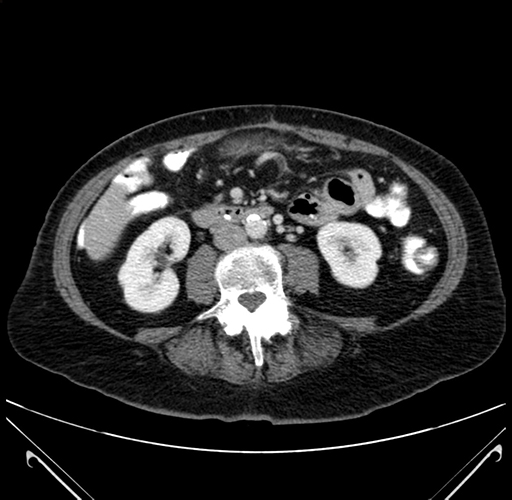

Pre-Chemo: Axial Venous

Axial Venous